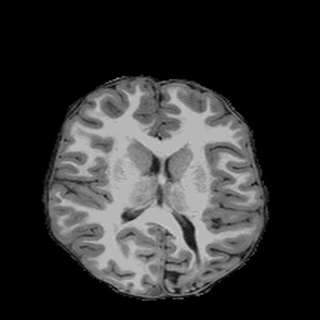

Tomographic image reconstruction is generally an ill-posed linear inverse problem. Such ill-posed inverse problems are typically regularized using prior knowledge of the sought-after object property. Recently, deep neural networks have been actively investigated for regularizing image reconstruction problems by learning a prior for the object properties from training images. However, an analysis of the prior information learned by these deep networks and their ability to generalize to data that may lie outside the training distribution is still being explored. An inaccurate prior might lead to false structures being hallucinated in the reconstructed image and that is a cause for serious concern in medical imaging. In this work, we propose to illustrate the effect of the prior imposed by a reconstruction method by decomposing the image estimate into generalized measurement and null components. The concept of a hallucination map is introduced for the general purpose of understanding the effect of the prior in regularized reconstruction methods. Numerical studies are conducted corresponding to a stylized tomographic imaging modality. The behavior of different reconstruction methods under the proposed formalism is discussed with the help of the numerical studies.

翻译:地形图象的重建一般是一个错误的线性反向问题,这种错误的反向问题通常利用事先对寻求的物体财产的了解加以规范化。最近,深神经网络通过从培训图像中学习物体属性的事先知识,积极调查使图像重建问题正规化;然而,对这些深网络所学的先前信息及其对可能存在于培训分发之外的数据进行概括化的能力的分析仍在探讨之中。以前不准确的情况可能导致在重建的图像中出现假结构,并引起医疗成像的严重关切。在这项工作中,我们提议通过将图像估计分解为一般测量和无效组成部分来说明重建方法以前强加的图象重建方法的效果。引入幻觉图的概念是为了了解在常规化的重建方法中以前的效果的一般目的。进行数量学研究时,与一种结构化的成像模式相对应。拟议形式下的不同重建方法的行为在数字研究的帮助下得到了讨论。